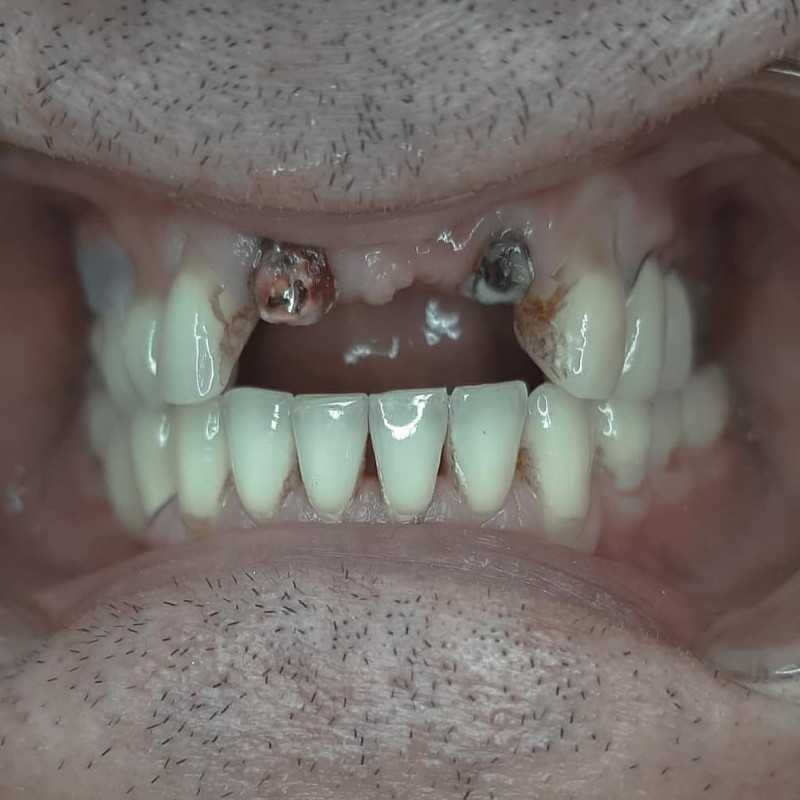

Жалобы: на отсутствие зубов, неудовлетворительную эстетику зубных рядов, невозможность жевать, подвижность зубов. Что сделано: удаление зубов на в/ч и н/ч, установка имплантатов Bredent Sky (верхняя челюсть 6 импл, нижняя 4 импл) и одномоментное протезирование акриловыми протезами с опорой на имплантаты по протоколу Fast & Fixed (зубы за один день). Через 10 месяцев проведена работа по замене протезов на постоянные металлокерамические. Что получил пациент: красивую улыбку, возможность нормально питаться с первого дня после операции.